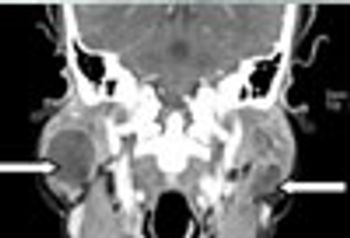

Lymphoepithelial cysts of the parotid gland may be diagnostic of HIV infection; they are typically bilateral, benign, and associated with lymphadenopathy.